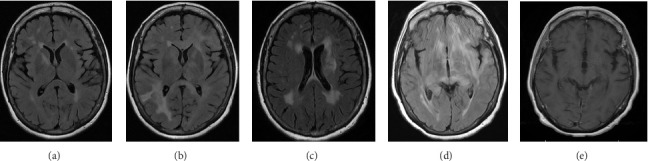

Primary central nervous system lymphoma (PCNSL) is a rare brain cancer that sometimes presented as rapidly progressive dementia. Diagnosing PCNSL presenting with rapidly progressive neurocognitive symptoms can be challenging, especially when the patient was previously treated with immunosuppressants for suspected autoimmune processes. We present a case where PCNLS was eventually and successfully treated 18 months after neurological symptoms started.